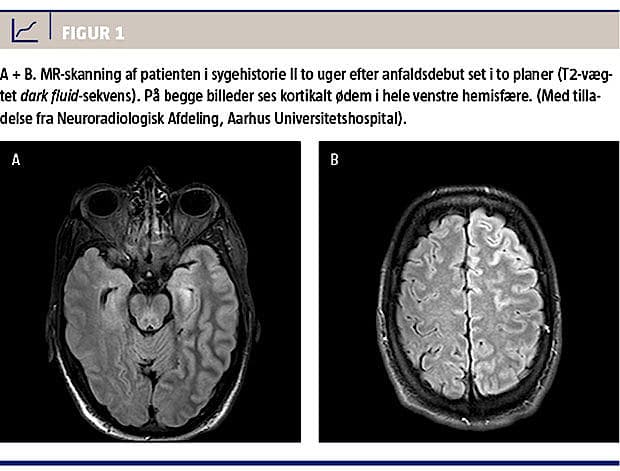

Patienten blev genindlagt, da han var 44 år, med bevidsthedssvækkelse, afasi og hemiparese, igen højfebril og med enkelte krampeanfald. MR-skanninger af cerebrum viste normale forhold ved indlæggelsen, men viste efterfølgende kortikalt ødem i hele venstre hemisfære (Figur 1). Han måtte igen overflyttes til en neurohabiliteringsafdeling. Han havde ikke haft migrænesymptomer imellem disse tilfælde.